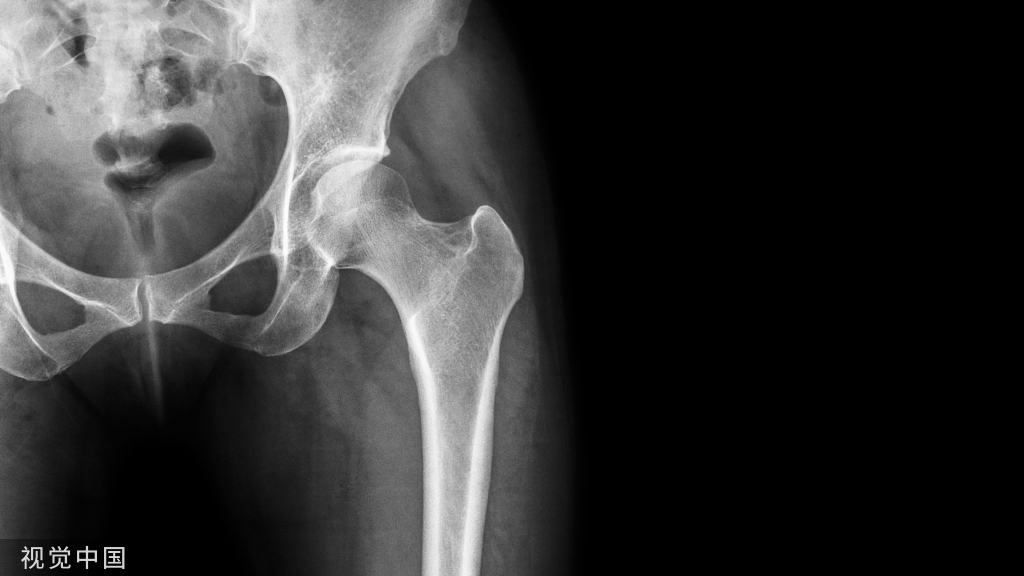

一、髋部骨折

髋部骨折主要指髋臼骨折和股骨近端骨折,具体包括髋臼骨折、股骨头骨折、股骨颈骨折、股骨转子间骨折和股骨转子下骨折,其中股骨颈骨折和股骨转子间骨折是最常见的骨折类型。

老年髋部骨折常发生在股骨近端,主要包括股骨颈骨折与股骨转子间骨折,约占老年髋部骨折的90%以上

图1 股骨近端示意图a.股骨近端正位图;b.股骨近端侧位图